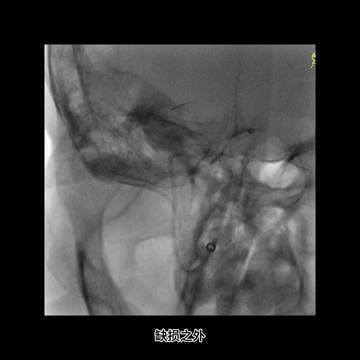

血栓坚硬,微导丝最终成袢通过闭塞位置,微导管跟进进入M1,释放支架。

抽拉结合取栓后造影:颈内动脉远端和M1多发充盈缺损;更换6F中间管,且6F长鞘上高到C1远端。

微导丝微导管超选到M1下干。